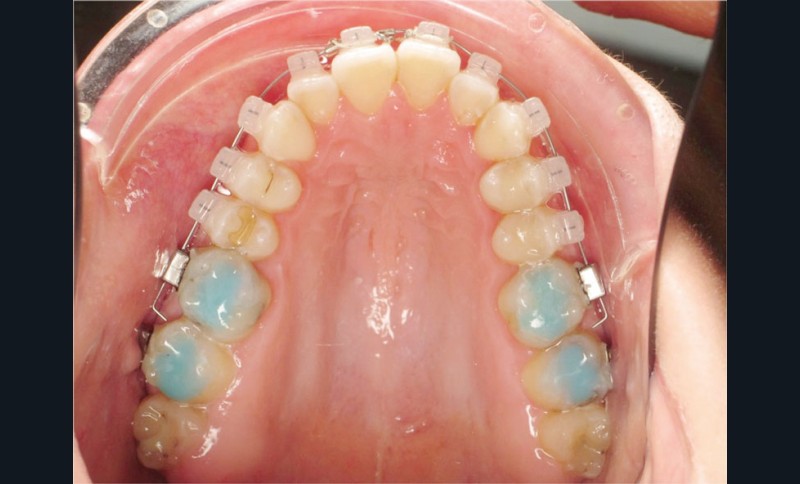

Des surélévations postérieures par cales sont posées et nous avons prévu un port d’élastiques précoce 23 heures sur 24.

Les empreintes ont été réalisées en sillcone wash technique et adressées au laboratoire Insignia. Actuellement, nous réalisons ces empreintes à l’aide de la caméra intra-orale Lythos et la fiche patient est initialement créée sur la caméra. Le transfert des empreintes au laboratoire est immédiat et le risque d’erreurs considérablement réduit (fig. 4 à 6).